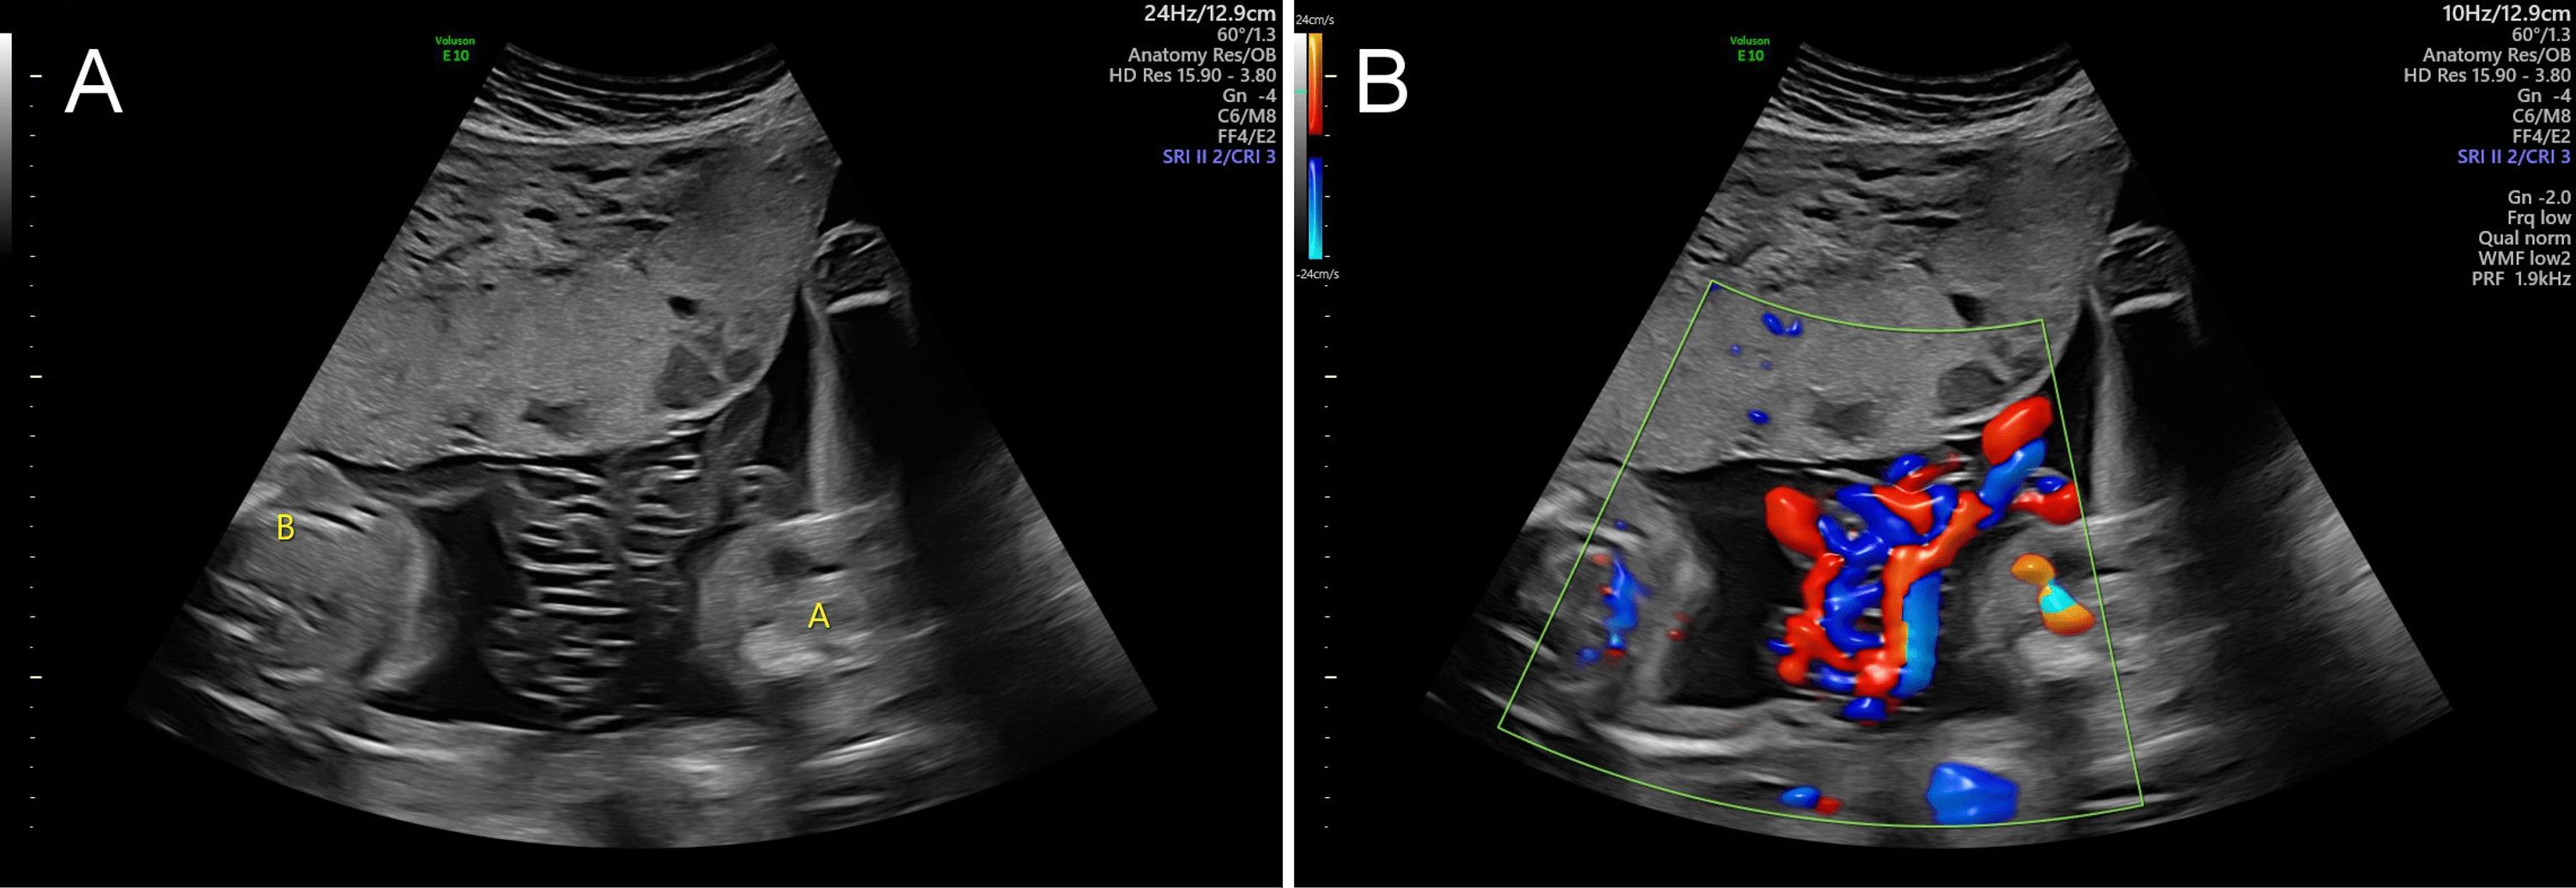

Ultrasound scan of cord entanglement. Download Scientific Diagram What Is Cord Entanglement   cord entanglement results from active fetal mobility and is facilitated by abundant amniotic fluid (especially if there is.   umbilical cord entanglement is the most common pathological condition among umbilical cord abnormalities [1],. Symptoms present in the baby shortly.   umbilical cord entanglement is present in all monoamniotic twins when it is systematically evaluated by ultrasound and color doppler.. What Is Cord Entanglement.

umbilical cord entanglement pacs What Is Cord Entanglement  Symptoms present in the baby shortly.   umbilical cord entanglement is present in all monoamniotic twins when it is systematically evaluated by ultrasound and color doppler.  cord entanglement is defined as an umbilical cord that encircles the fetal body, neck, or extremities [1].   umbilical cord entanglement is the most common pathological condition among umbilical cord abnormalities [1],. . What Is Cord Entanglement.